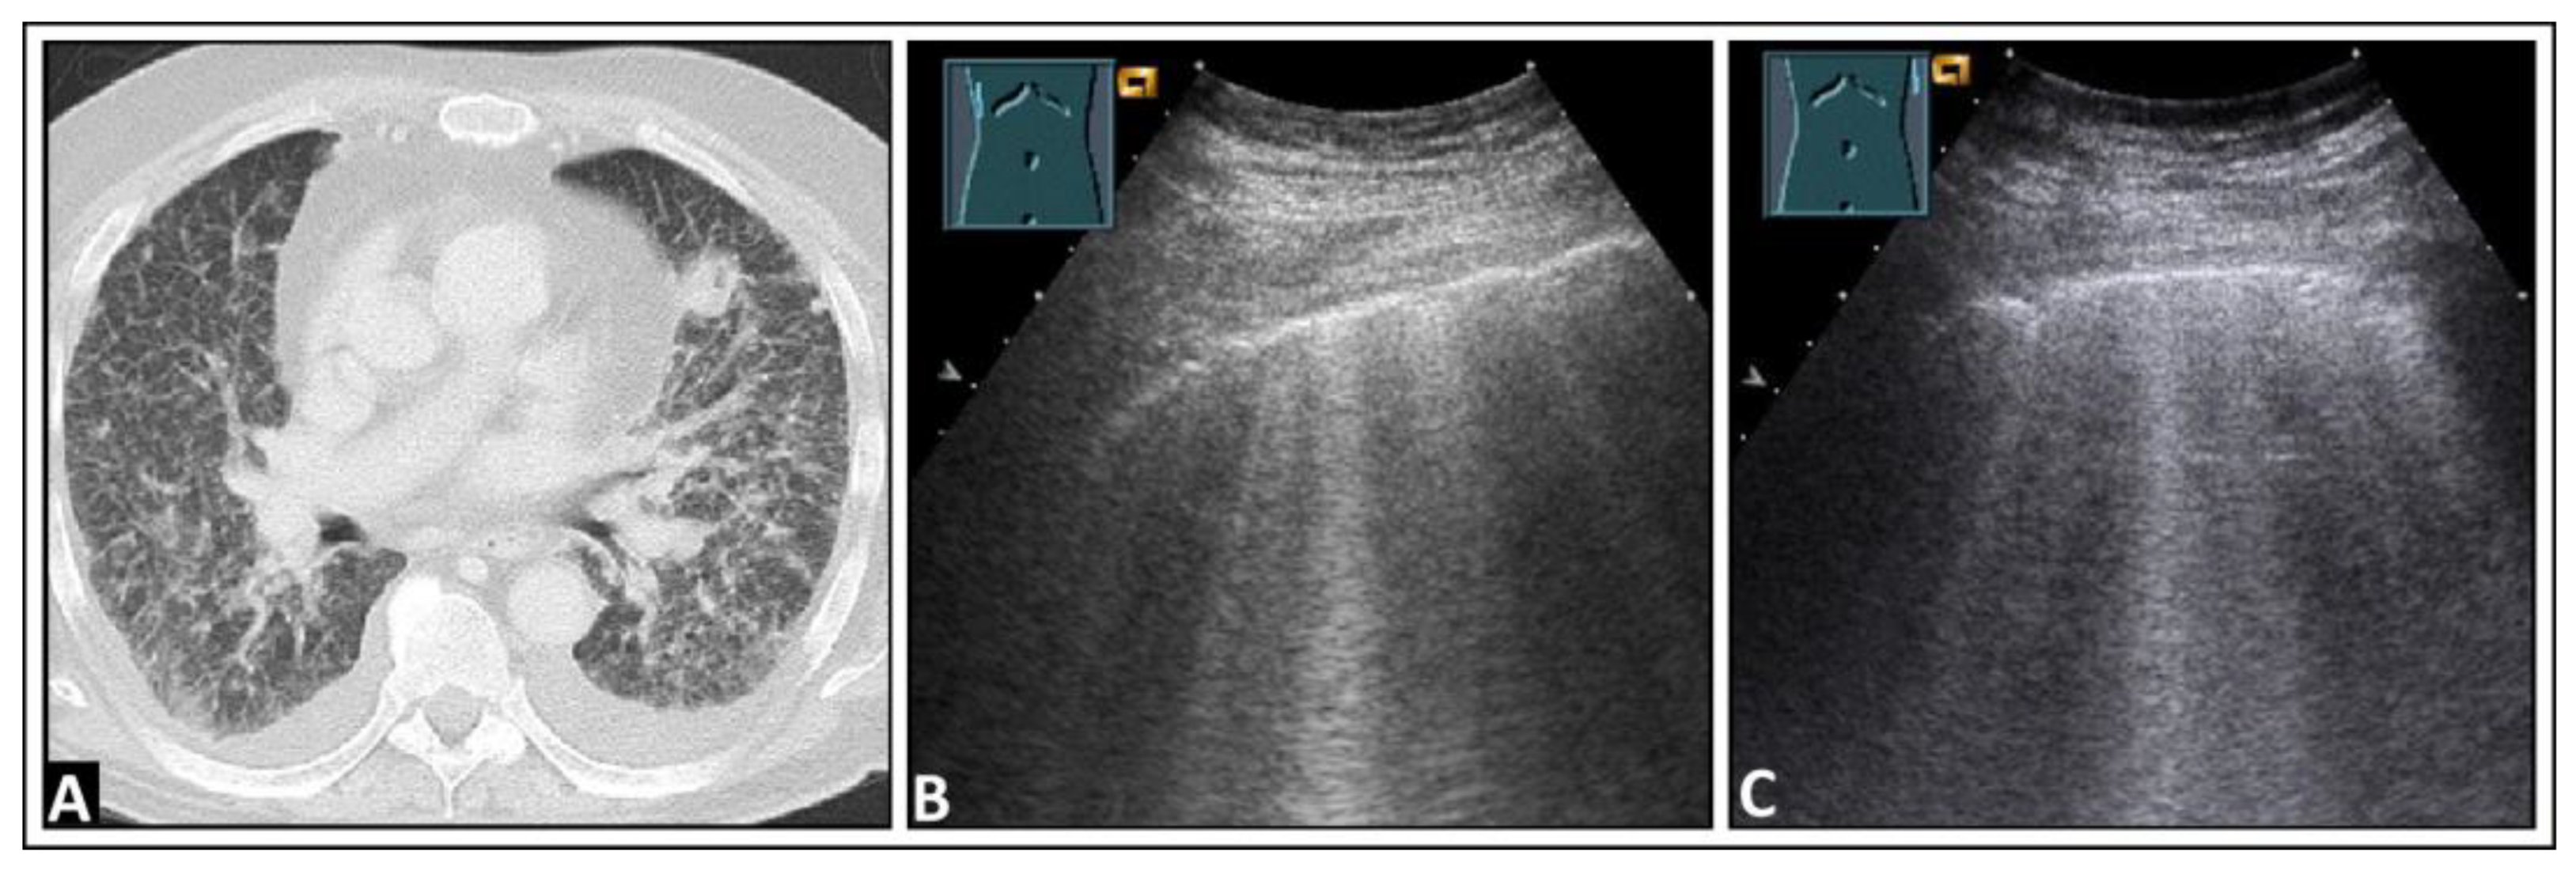

5. Pneumonia